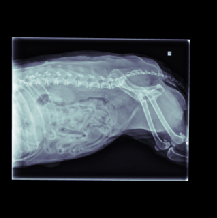

The data for this work consists of 390850 X-ray images, taken from 98660 veterinary sessions. These images were annotated by radiologists for over 41 diseases in a multi-label fashion, and are feedback from the usage of the RapidRead tool. Additionally, we have a dataset of 800 images with high-quality annotations, where the annotations were performed by 12 radiologists collaborating on each image. A sample of these X-ray images is shown in Figure 2.

This section presents visualizations of the Vision Transformer (ViT) attention maps. The ViT used is specific to lung diseases, and the attention maps are shown for patients with the positive label ’Pulmonary Mass’. The input to the ViT is a concatenated feature map, and the X-ray images have been mapped and displayed with the same concatenation and transformations applied to the augmented feature maps.

The attention maps show that the ViT focuses on the thorax region where the lungs are located, as expected. The results also demonstrate that the ViT remains focused on the thorax area even with different contexts in the X-ray images. This highlights the robustness of ViTs.